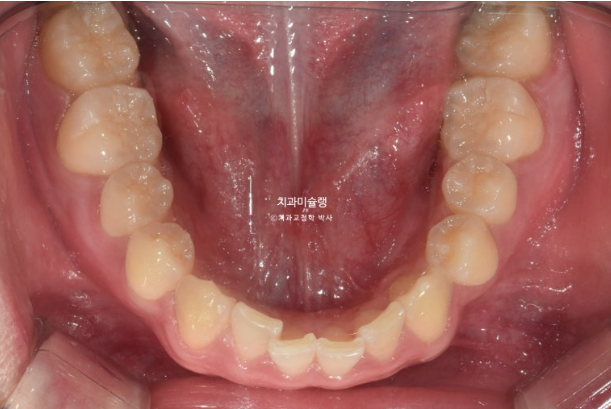

오늘은 가위교합, 중심선 이슈, 거미스마일 등등에 왜소치까지 있는 복잡한 케이스를 인비절라인으로 어떻게 치료하는 지 보여드리겠습니다.

2022년 10월 비대칭으로 내원하신 분입니다.

중심선 불일치, 왜소치로 인한 벌어짐, 송곳니 덧니 등이 보입니다.

이 환자분이 한쪽으로만 씹었던 이유는 반대쪽에 가위교합이 있었기 때문입니다.

파란 화살표가 가위교합이고 위 큰어금니는 바깥으로 나가있고 대합치는 안쪽으로 쓰러지며 가위처럼 서로 엇갈려 교합되는 상태를 말합니다.

파란 화살표 치아가 바깥으로 뻗치면서 가위교합의 원인이 됩니다.